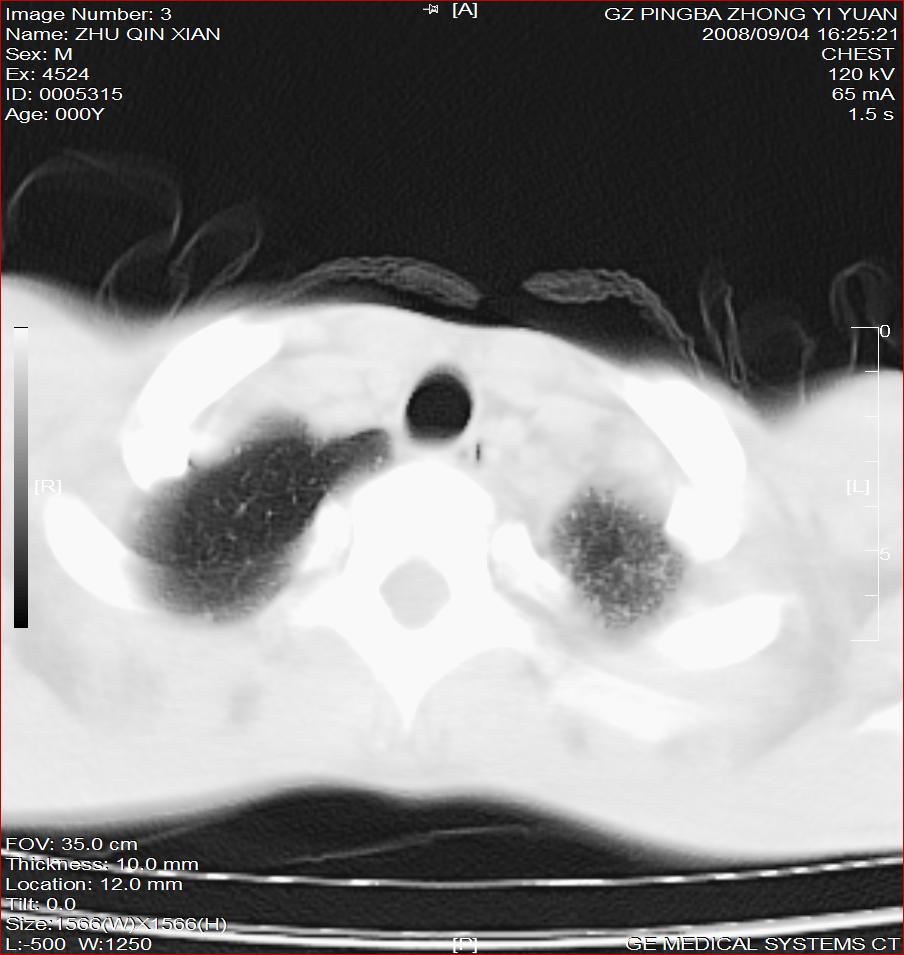

以下是引用随光逐影在2008-9-4 20:05:00的发言:[br]1)考虑两肺结核。2)左侧胸膜炎(胸膜肥厚、粘连,胸腔积液)。3)左侧局限性气胸。

以下是引用子十在2008-9-4 19:34:00的发言:[br]左上肺结核并空洞及双肺播散。节段性肺不张、胸腔积液、胸膜肥厚粘连。[br]